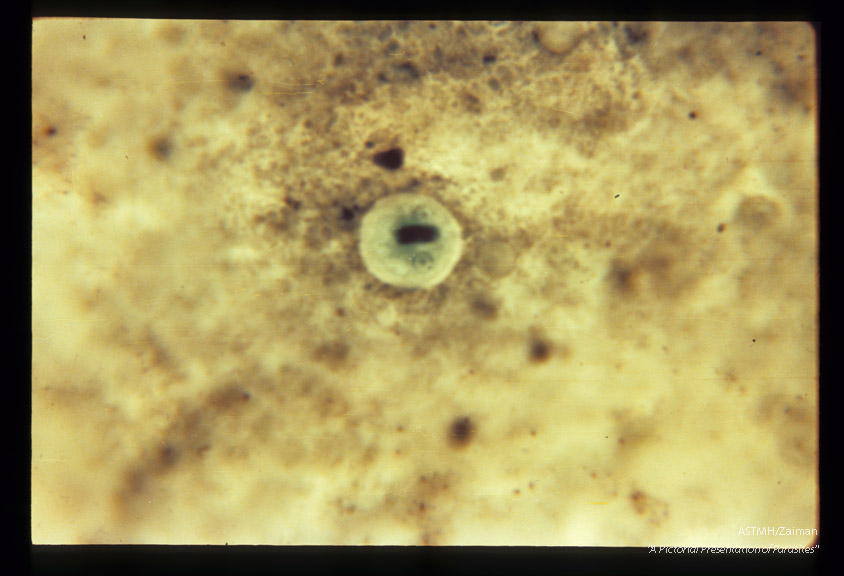

Cysts in stool. Chlorazol black stain.

Entamoeba histolytica

Description: Cysts in stool. Chlorazol black stain.